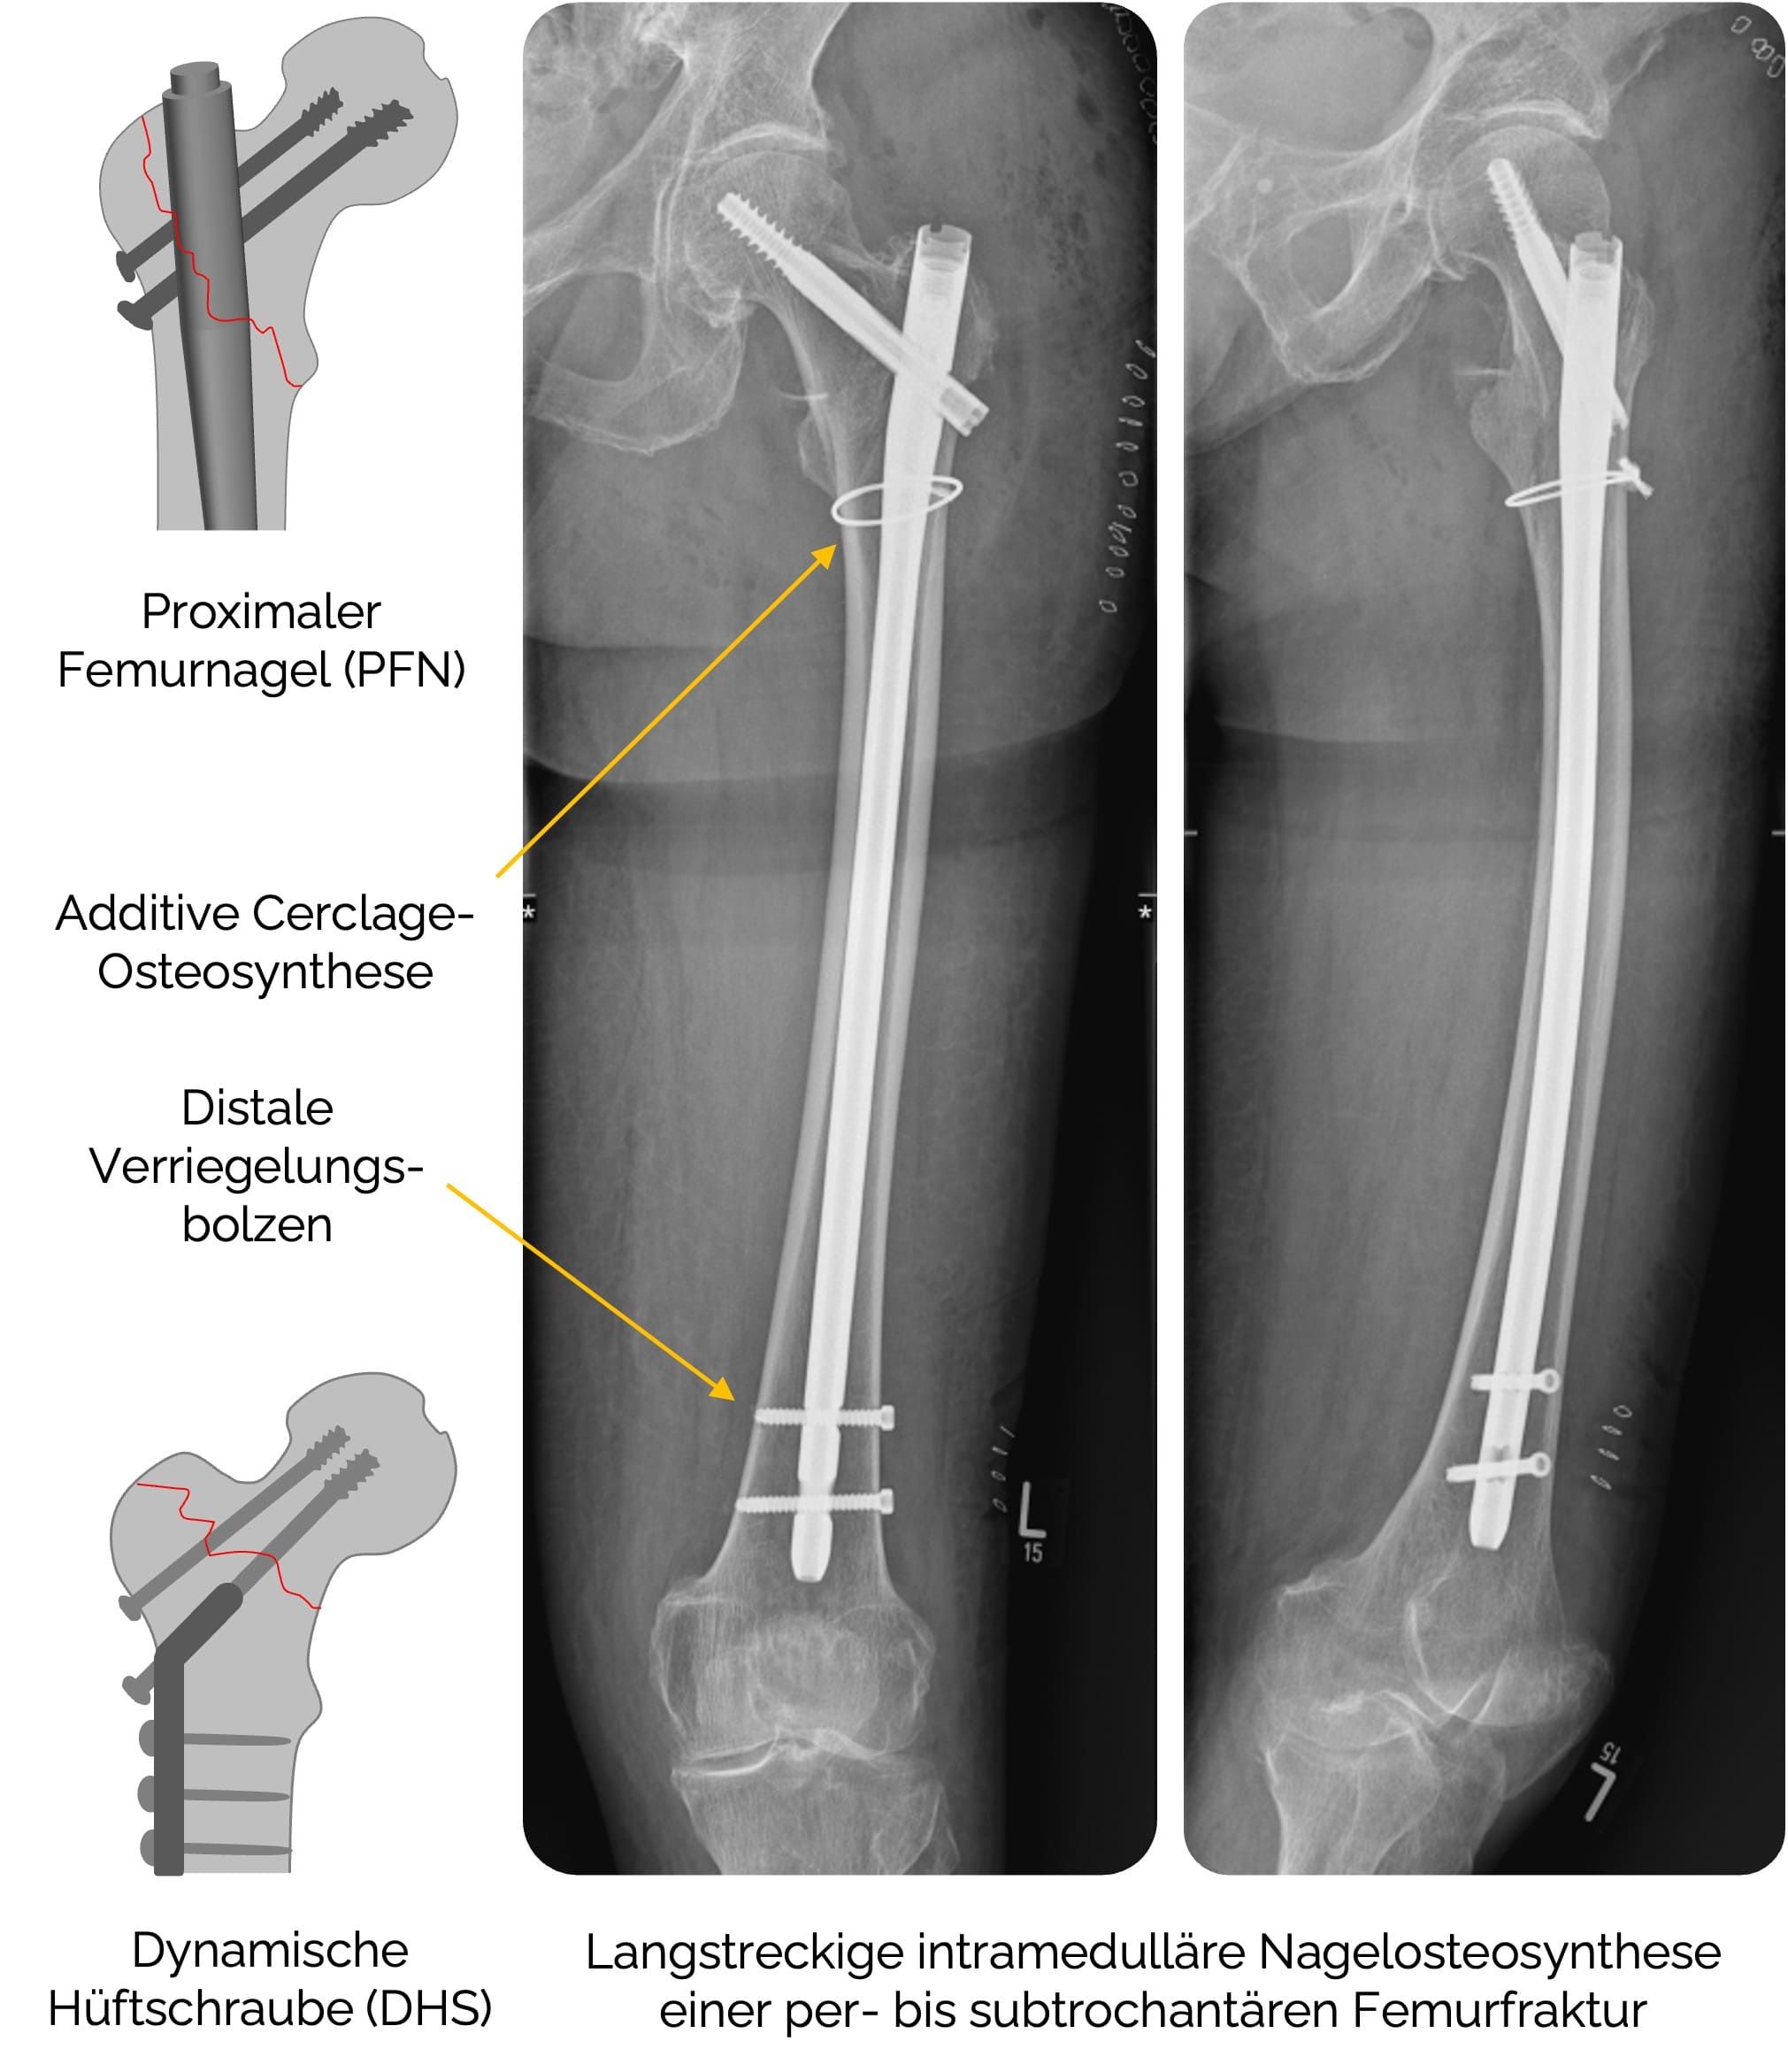

Die pertrochantären Frakturen werden wie die Schenkelhalsfrakturen operativ versorgt. Während stabile Frakturen mit extramedullärer Osteosynthese versorgt werden können, stellt die intramedulläre Nagelosteosynthese

- Intra- / zephalomedulläre Nagelosteosynthese

z.B. PFT, TFN, Gamma-Nagel (prinzipiell bei allen pertrochantären Frakturen, besonders bei instabilen Frakturen AO 31A2-A3 und bei inter- / subtrochantären Frakturen mit langem Nagel) - Ggf. Fragmentfixierung mittels additiver Draht- / Cerclage-Osteosynthese

- Geschlossene Reposition mit Marknagelosteosynthese (Goldstandard) und Verriegelungsbolzen zur Rotationsstabilität. Statisch oder dynamisch mit oder ohne Markraumbohrung, teilweise additive Cerclage-Osteosynthese.